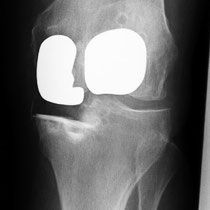

Auch bei dem künstlichen Ersatz des Kniegelenkes muss genau abgewogen werden, was eingentlich ersetzt werden muss. Je weniger ersetzt wird umso besser im Gesamtergebnis. Warum soll man das ganze Knie ersetzen, wenn nur der Knorpel unter der Kniescheibe zerstört ist (Bild 3 Kniescheiben - und Gleitlagerersatz). Anders bei schwerer Rheumazerstörung, bei der alle Bänder ausgelockert sind - hier wäre die normale Knieprothese auch locker (Bild 5 Lösung: achsgekoppelte Prothese). Ich versuche für meine Patienten das bestmögliche Implantat auszusuchen. Für Allergiker stehen spezielle titanbeschichtete Kniegelenke zur Verfügung.